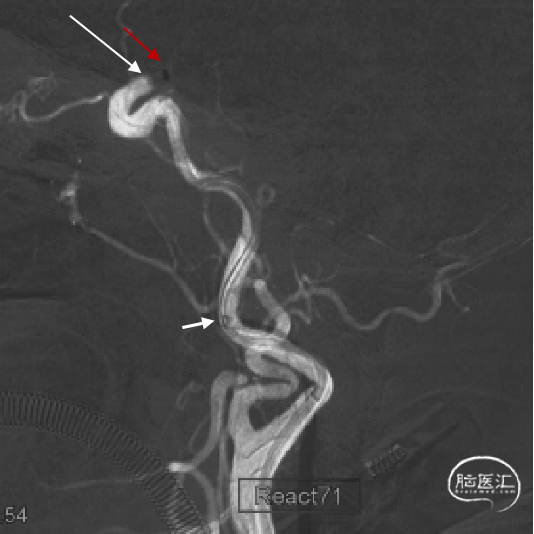

长鞘跟过颈内动脉起始部弯曲段后,在持续负压抽吸下,微导管微导丝顺利辅助抽吸导管通过海绵窦段至闭塞段以远接触血栓(红色箭头所示为导管头端,白色长箭头所示为路图下闭塞段;白色短箭头为长鞘位置)。

不减影图像中长鞘(白色箭头)和抽吸导管(红色箭头)位

侧位:抽吸导管到位、接触抽吸过程。

持续接触抽吸90秒后,回撤抽吸导管;抽吸导管进入长鞘之前,开启长鞘负压抽吸;发现血栓卡在长鞘头端、抽吸导管撤出长鞘后发现长鞘内无回血(白色短箭头)。20ml注射器连接长鞘、持续负压抽吸下撤出长鞘;长鞘在进入8F穿刺鞘前,开启穿刺鞘负压抽吸(白色长箭头)。最终成功将血栓从长鞘内抽吸出。